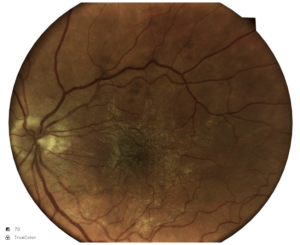

Retinografia colorida do olho esquerdo: observa-se a presença de membrana epirretiniana na região macular, com brilho reflexivo superficial e pregueamento das camadas internas da retina, determinando distorsão do reflexo foveal compatível com pucker macular. Vasos retinianos apresentam leve tortuosidade na área acometida.